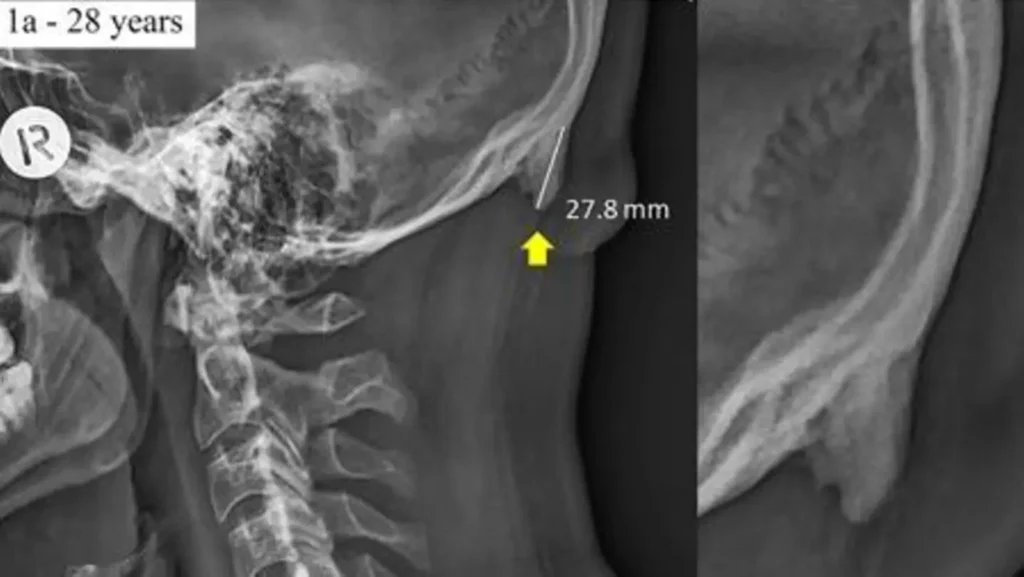

- Röntgenbild: Ein Röntgenbild zeigt die Struktur des Schädelknochens und kann Hinweise auf eine Fraktur oder andere Veränderungen geben.

- Computertomographie (CT): Eine CT-Untersuchung liefert detaillierte dreidimensionale Bilder des Schädels und kann helfen, die Ursache der Beule genauer zu bestimmen.